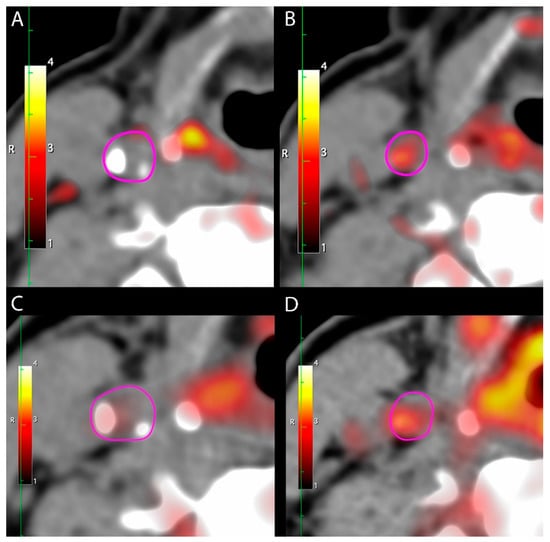

3.2. [64Cu]DOTATATE Uptake in Carotid Arteries

3.3. [64Cu]DOTATATE Uptake vs. [18F]FDG Uptake in Carotid Arteries